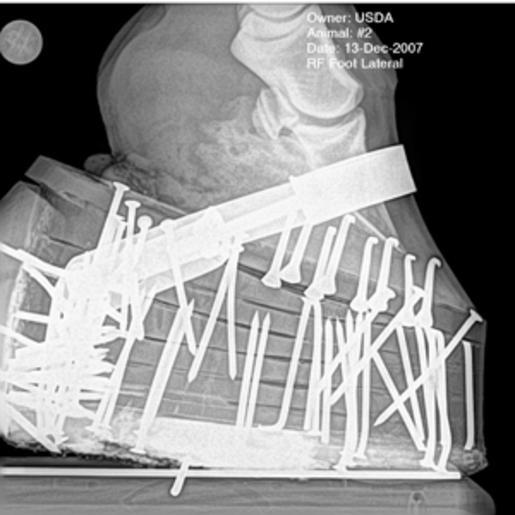

MAKE A MEME View Large Image Xray-USDA.gif en X-Ray image of a performance package on a Tennessee Walking Horse showing shoe stacks - the multiple pads multiple extra nails placed in pads to add weight and possibly pressure known as pressure soring and band across hoof ...

Keywords: Xray-USDA.gif en X-Ray image of a performance package on a Tennessee Walking Horse showing shoe stacks - the multiple pads multiple extra nails placed in pads to add weight and possibly pressure known as pressure soring and band across hoof to hold it all on 2013-03-19 07 59 43 USDA http //www chattanoogan com/2012/7/28/231181/Roy-Exum-Horse-Abuse-Just-Dial-911 aspx and http //atwork avma org/2011/11/09/progress-on-soring-and-kudos-to-usda/ United States Department of Agriculture Source viewed http //atwork avma org/2011/11/09/progress-on-soring-and-kudos-to-usda/ PD-USGov Uploaded with UploadWizard Tennessee Walking Horse Horse abuse Horseshoes